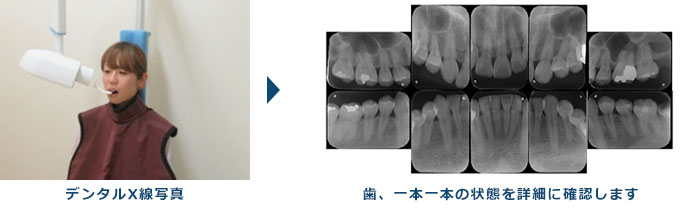

3.エックス線検査

歯周病が進行すると、歯を支えている歯槽骨が溶けてきますので、歯肉の下にある歯槽骨の高さを調べることも必要になります。

歯槽骨の状態を調べるのに最も効果的な検査がエックス線検査です。

エックス線検査は、歯槽骨の溶けてなくなった範囲や程度をかなり正確に知ることのできる検査になります。

当院では「SIRONA社製 ORTHOPHOS XG」というデジタルエックス線撮影機を使用しており、皆さんが気にされている撮影時の被爆量が最小限で、かつ高精細な画像が得られるように配慮しております。